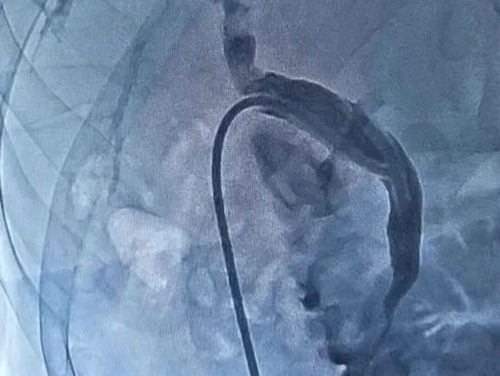

栓塞后出血停止

▲ 栓塞后肝动脉出血停止